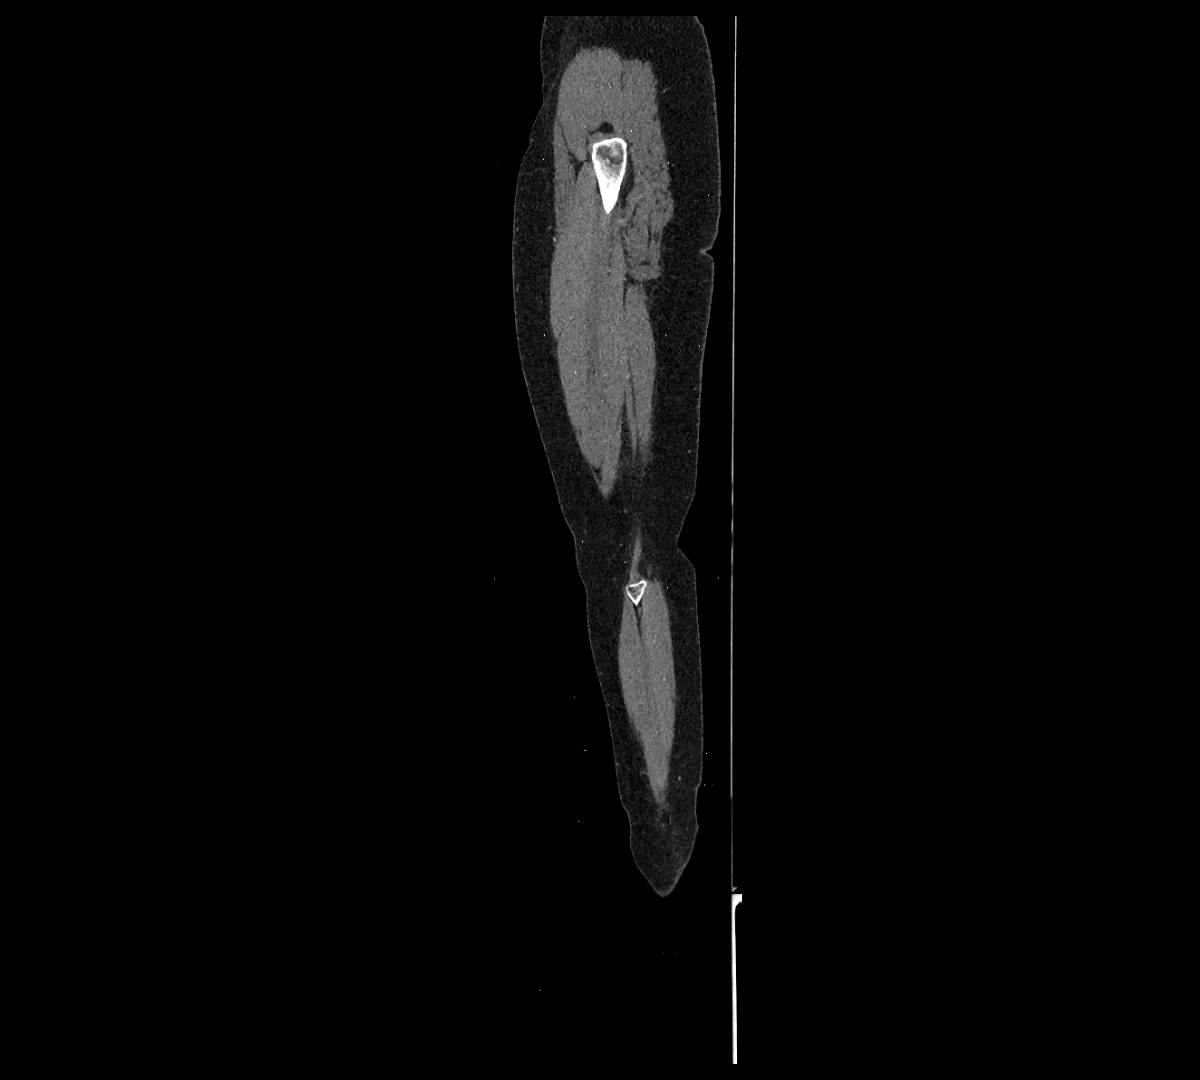

MRI images

image